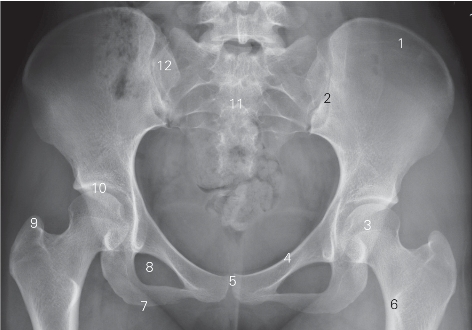

图7-5 骨盆正位DR平片

1 髂骨翼 ala of ilium 2 骶髂关节 sacroiliac joint

3 股骨头 femoral head 4 耻骨上支 superior ramus of pubis

5 耻骨联合 symphysis pubis

6 股骨小转子 lesser trochanter of femur

7 坐骨结节 ischial tuberosity 8 闭孔 obtur ator formamen

9 股骨大转子 greater trochanter of femur 10 髋关节 hip joint

11 骶骨 sacrum 12 骶骨翼 sacral wing